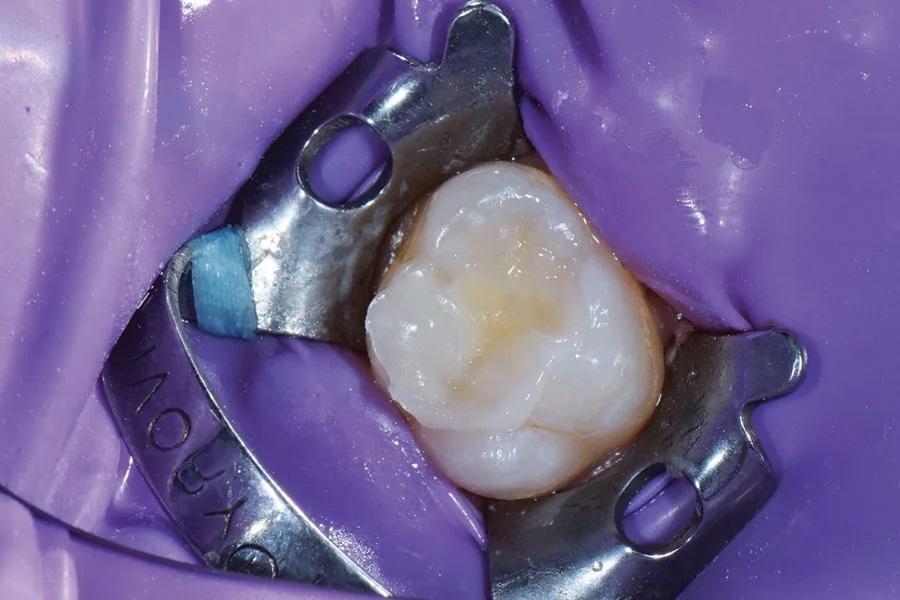

На зуб 2.6 нанесена жидкость для выявления кариеса (Snoop, Pulpdent) для визуализации пораженных участков (Фото 5). Дентиновые кариозные ткани удалены на окклюзионной поверхности зуба № 14 карбидным бором № 557 (Straight Carbide Bur, Brasseler USA) в электрическом наконечнике (Forza, Brasseler USA) (Фото 6).

Фото 5. На зуб 2.6 была нанесена жидкость для определения кариеса, чтобы осветить участки кариозных поражений для удаления.

Фото 6. Окончательное препарирование после подтвержденного полного удаления кариеса.